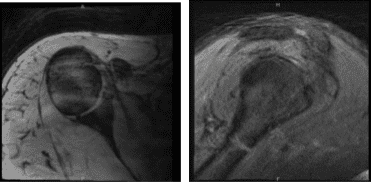

He came into our office with recurrent right shoulder recurrent pain which has not been getting better. The patient was weak in his rotator cuff muscles. The patient presented an MRI result and showed that it was normal but there was a high suspicion of rotator cuff tear.

MRI-3T Right Shoulder non-contrast

An MRI result was presented which showed biceps tenodesis and possible tear in the rotator cuff. Evidence of prior rotator cuff repair with suture anchor in the greater tuberosity. However, findings compatible with a recurrent tear of the supraspinatus at least moderate severity.

Low-grade partial thickness tear of the subscapularis tendon. Biceps tendinosis and tenosynovitis without tears. Findings suggesting adhesive capsulitis. Small tear at the base of the anterior labrum. Mild bursitis.